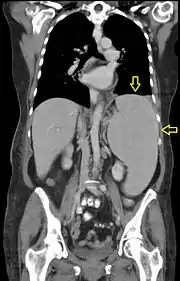

Syndrome tumoral

Le syndrome tumoral est lié à la dissémination des blastes hors de la moelle osseuses et de la accumulation dans les organes. Il peut se traduire cliniquement par[31] :

- une augmentation de volume de certains organes : splénomégalie, hépatomégalie ;

Le syndrome de leucostase est observé en cas d'infiltration massive des organes par les cellules leucémiques. Il se manifeste par une forte concentration des blastes dans le sang (blastose), une fièvre et des symptômes respiratoires et ou neurologiques. Ce syndrome est une urgence thérapeutique dont l'issue peut être fatale par détresse respiratoire.